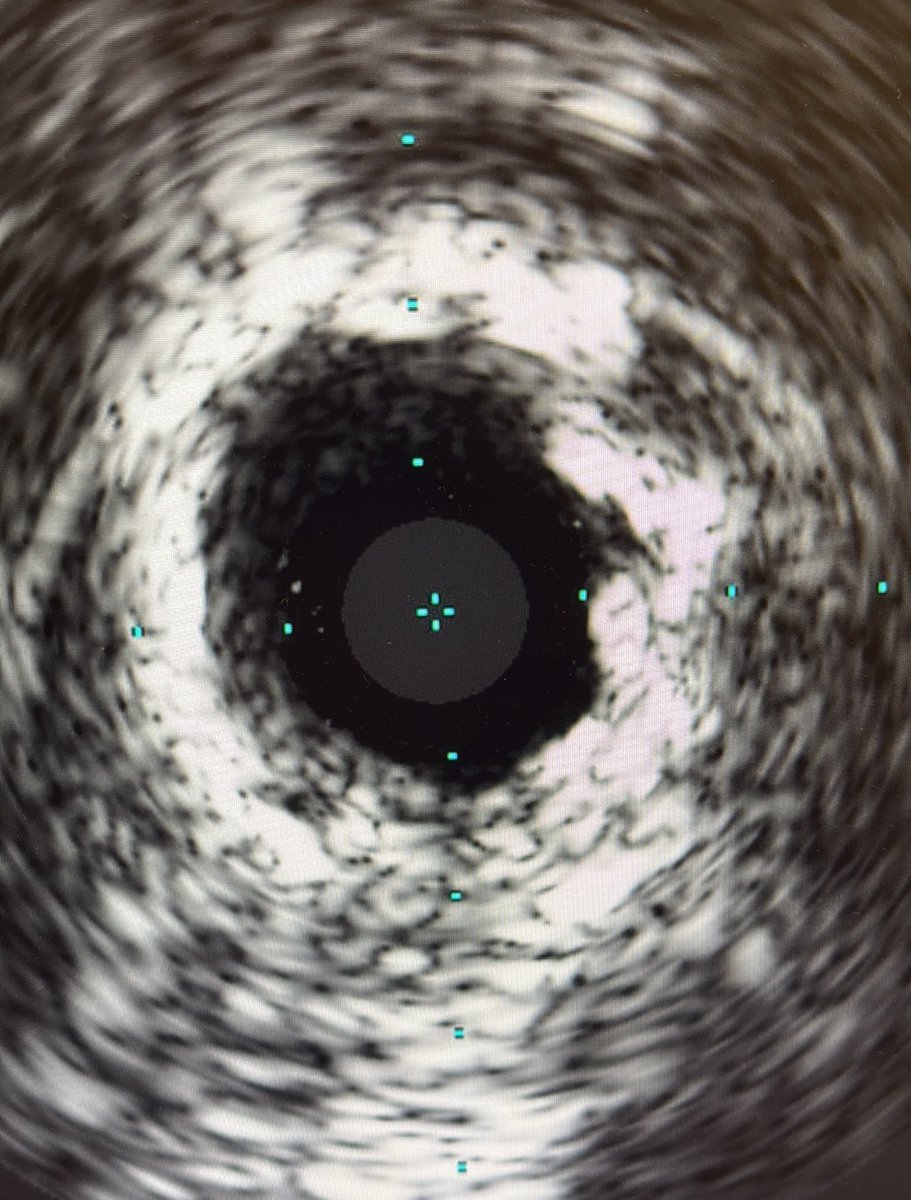

How to handle this? DCB available, FYI. @realarainmd @ShariqShamimMD @jl35wilsonMD @AuroraCVFellows @DanielJohnsrud @evandrofilhobr @RSohnMD @DrWhyWho @DrBIqbal @drAliyor @mornei2011 @SyedYNaqvi1

19

12

67

@jedicath @kerrigjl @kevinjamescroce @jl35wilsonMD @jbspadoni @aspergian1 @mornei2011 @DrIHHashmi1 @Hragy @toreyj01 @DrBIqbal @realarainmd (2/2). 🌋 is almost useless here IMHO.

2

1

6